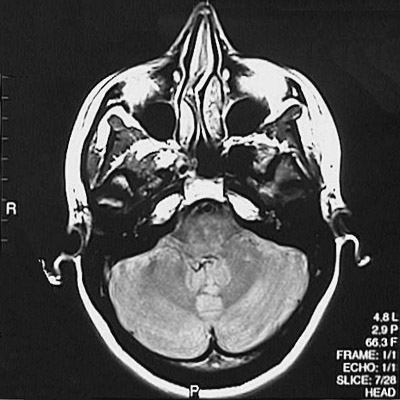

This is a normal axial proton density MRI scan demonstrating the nasal septum and concha and maxillary sinus and sphenoid sinus and medulla and fourth ventricle and cerebellar hemisphere and dentate nucleus.